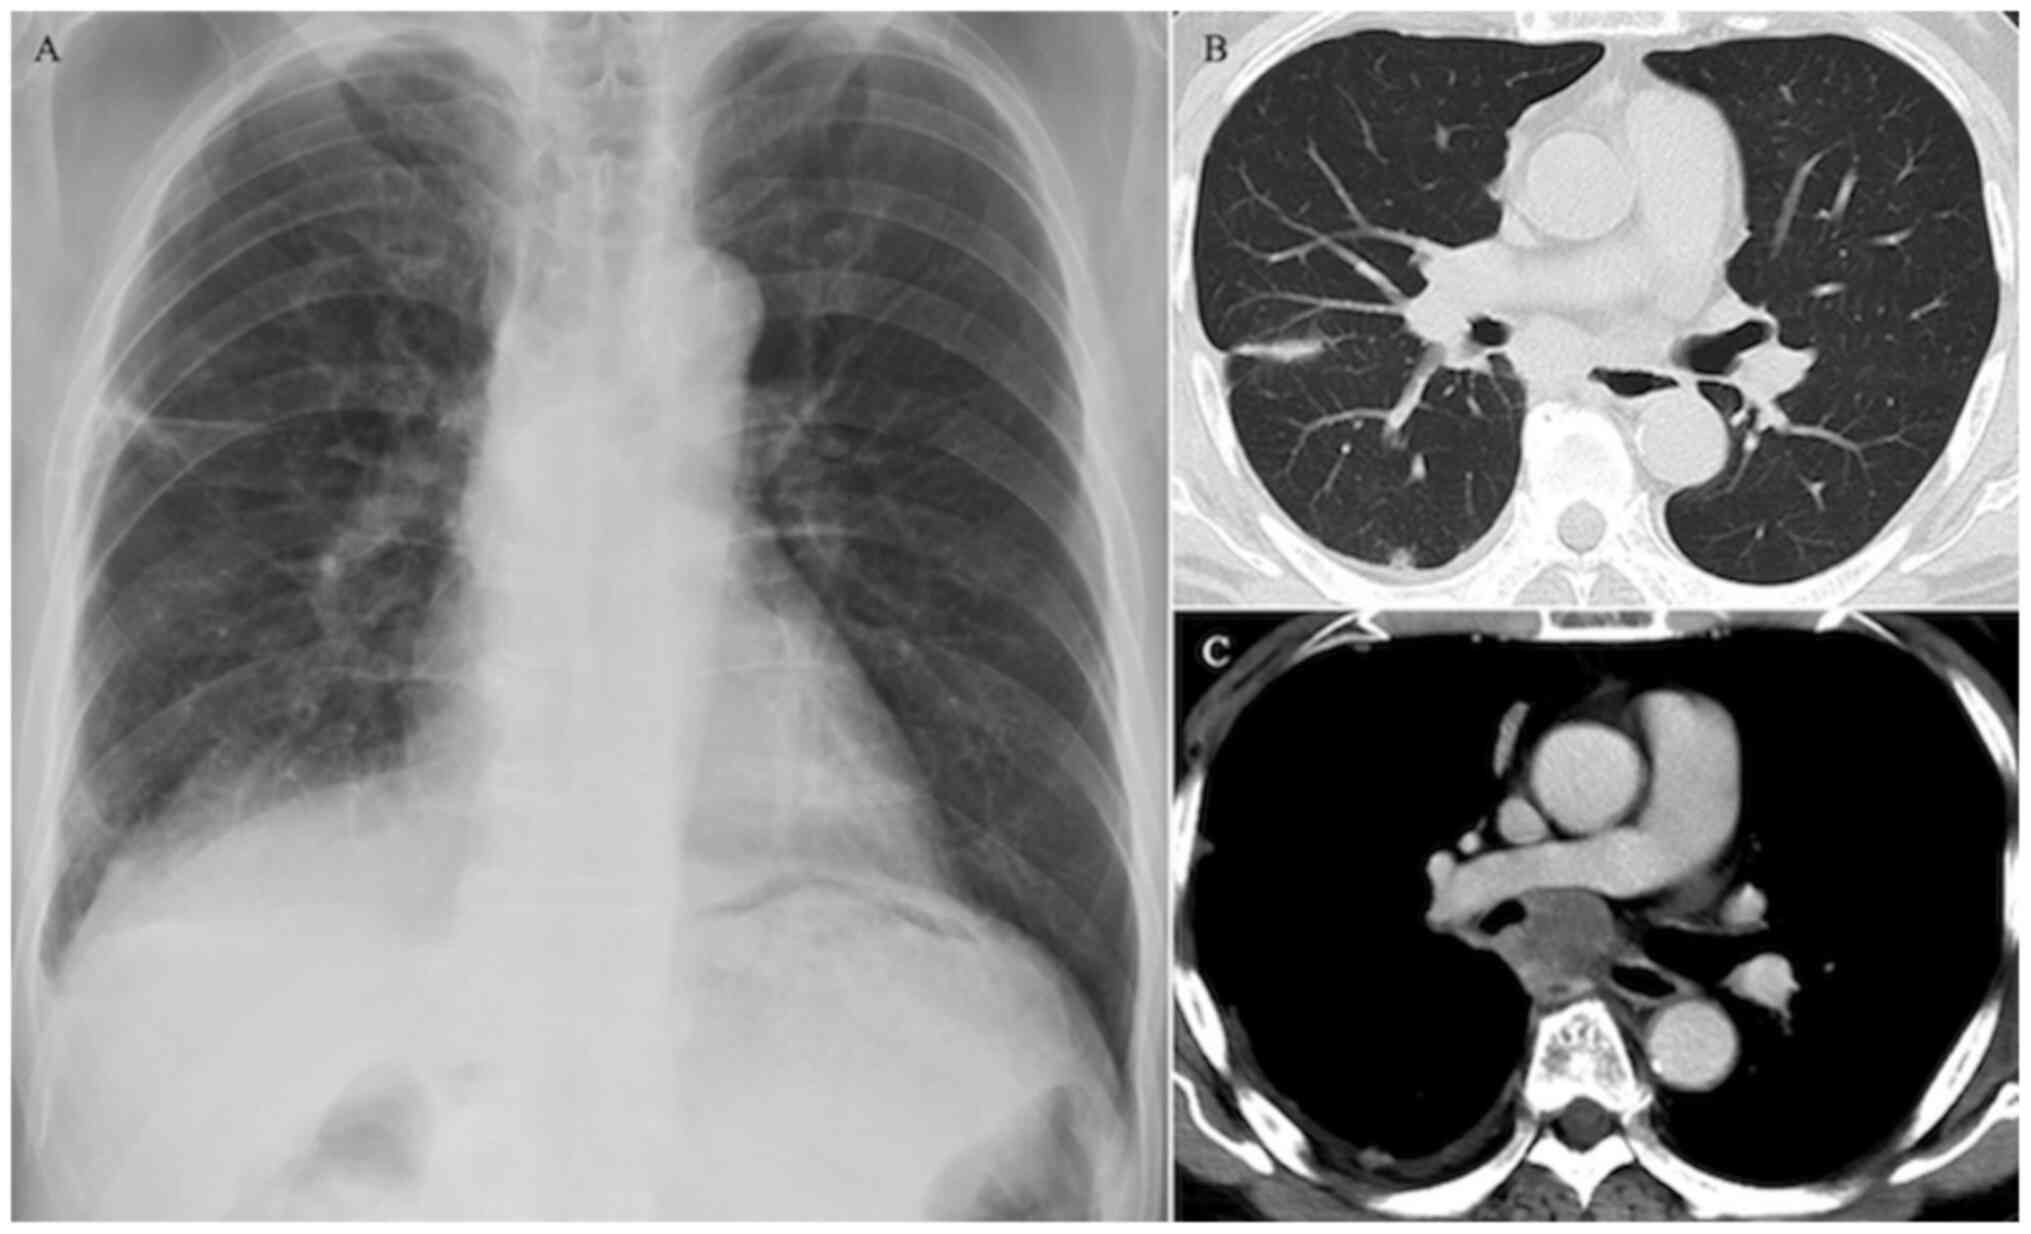

In August 2018, a 67-year-old Japanese man with a history of asthma and chronic obstructive pulmonary disease was referred to our hospital due to chest pain. Chest radiography revealed linear opacity in the right middle lung field (Fig. 1A). A chest CT scan revealed a 27-mm tumor in the subcarinal space, pleural invasion in the right upper and middle lung segments (Fig. 1B) and a hilar mass shadow with contrast enhancement along the right main bronchus from below the tracheal bifurcation (Fig. 1C). A brain contrast-enhanced MRI revealed two small nodules in the cerebellum and cerebrum (Fig. 2A and B). Fluorodeoxyglucose (FDG) positron emission tomography with CT revealed intense FDG accumulation in the subcarinal space and pleural nodule. Histological examination of the tumor in the transbronchial lung biopsy specimens from the subcarinal space revealed adenocarcinoma, with a tumor proportion score of 100% for programmed death-ligand (PD-L1) using a PD-L1 antibody (clone 22C3; Agilent Technologies, Inc.) and no expression of epidermal growth factor receptor (EGFR) mutation, anaplastic lymphoma kinase (ALK) fusion, ROS proto-oncogene 1, receptor tyrosine kinase (ROS1) fusion and B-Raf proto-oncogene, serine/threonine kinase (BRAF) mutation. Based on these findings, the patient was diagnosed with stage IVB lung adenocarcinoma (TxN2M1c, brain pleura).

Figure 1

Radiography and CT findings. (A) Chest radiography revealed linear opacity in the right middle lung field. (B) Trunk CT revealed multiple thickenings in the right pleura and right pleural effusion. (C) Trunk contrast-enhanced CT revealed a hilar mass shadow with contrast enhancement along the right main bronchus from below the tracheal bifurcation. There were no findings to explain the nausea, despite the slight thickening and contrast enhancement on the stomach wall. CT, computed tomography.